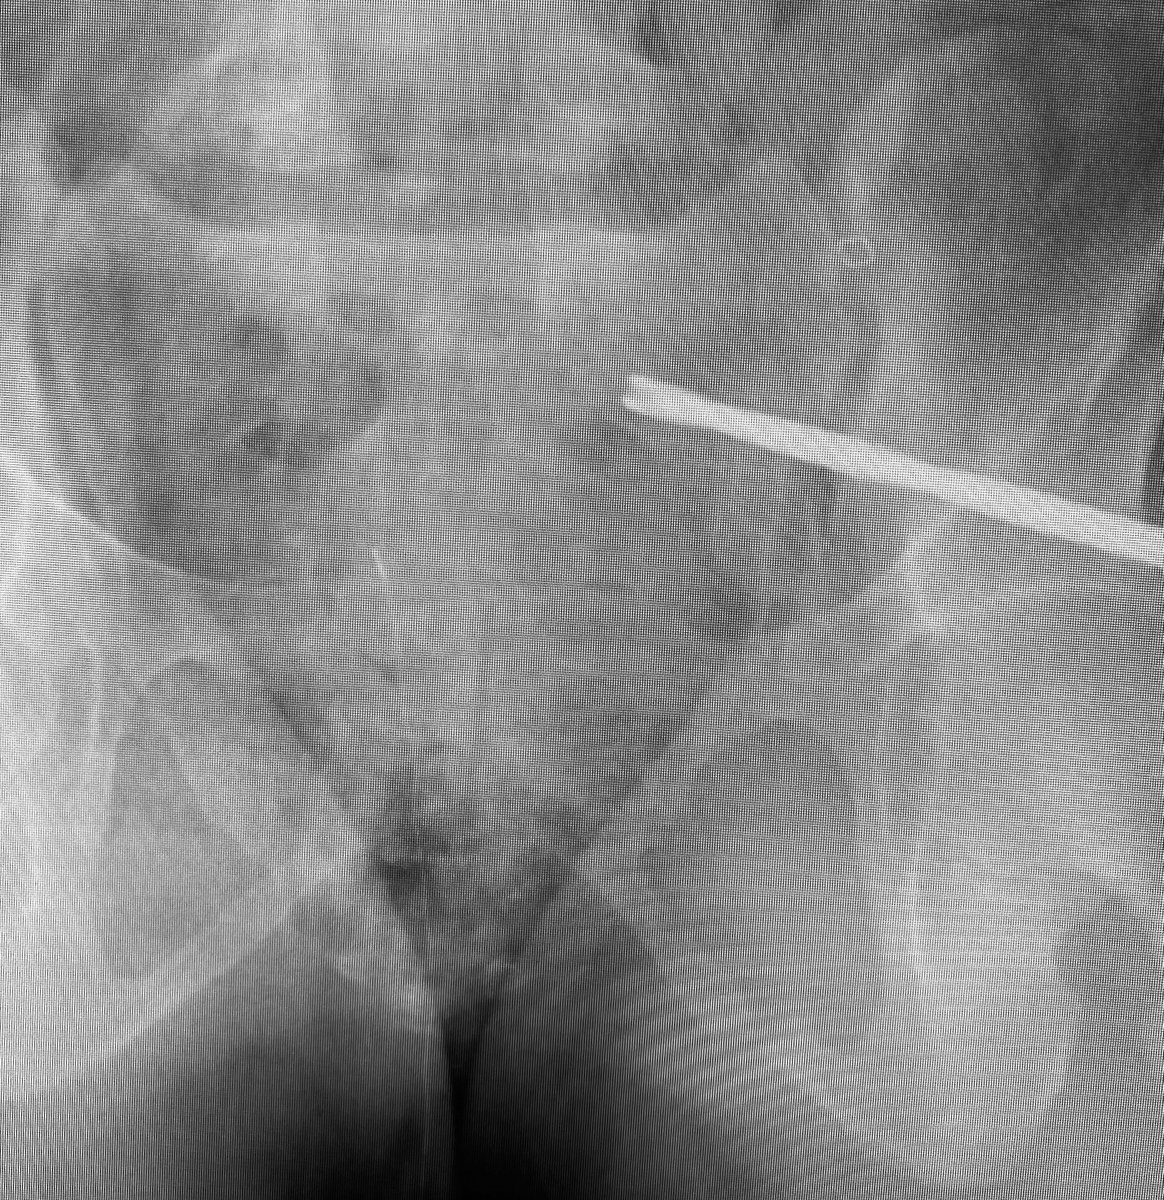

Control your iliosacral screw insertion precision by using an initial K wire to simply identify the optimal insertion site for your intended pathway-insert it 1-2cms then proceed directly to using the cannulated drill - the drill allows early slight corrections without deformity

Use the cannulated drill to avoid wayward misdirections from more flexible guide wires